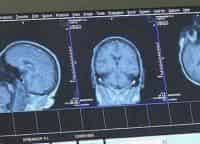

Владимир Рыбаков сегодня крепкий и здоровый мужчина. Но всего семь лет назад он перенес инсульт. Тогда у него была парализована половина тела, Владимир не мог разговаривать и даже глотать.

В больнице его навещал сосед, он же единственный друг - Александр. Александр все думал, как поставить соседа на ноги. И вспомнил слова его бабушки-травницы. Когда он был маленький, она водила его в лес, про травы и растения рассказывала: что и от какой болезни помогает. Александр вспомнил про настойку из сосновых шишек. Пошел в лес, собрал целое ведро шишек и поставил настаиваться на спиртовом растворе. До сих пор он этим средством еще никого не лечил. Сам переживал, не навредит ли? На всякий случай залез в Интернет, чтобы убедиться, что оно, по крайней мере, безопасно.

Народное лекарство пришлось вливать другу чуть ли не силком. Глотать он не мог, рот еле открывал. Через два дня Владимир ел самостоятельно и даже просил разрешить ему встать с кровати. А через пару месяцев он почувствовал себя здоровым. Все, что осталось от тяжелой болезни - метеочувствительность.

Что такого уникального содержится в шишках, что они могут поставить человека на ноги после инсульта? Оказывается, самое страшное - не сам инсульт, а его последствия. Ученые выяснили, что остановить гибель клеток мозга после инсульта способны особые вещества - танины. Они содержатся в виноградных косточках и еловых шишках.